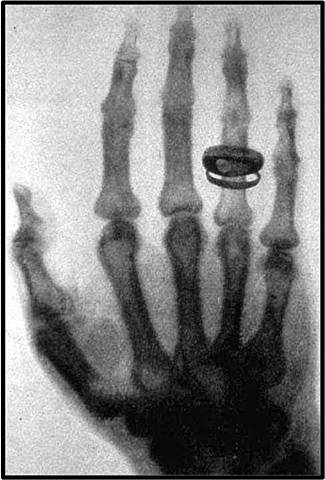

• Descubrimiento de los rayos X

Descubrimiento de los rayos X

Wilhelm Konrad Röntgen experimentaba con los rayos catódicos, cubrió un tubo de crookes con trozos de cartón negro, oscureció la habitación para probar opacidad de la cubierta de cartón negro. Después a un metro del tubo vio una luz. Emocionado, encendió una cerilla, descubrió la fuente de la luz era una pantalla de platino-cianuro de bario (solo emite luz utilizando luz ultravioleta). Los llamó rayos X, ya que los rayos eran de naturaleza desconocida.